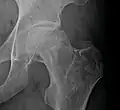

![]() | |

| Femoral head showing a flap of cartilage due to avascular necrosis (osteochondritis dissecans). Specimen removed during total hip replacement surgery. | |